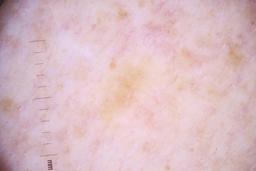

ISIC_4077341

Clinical

| Field | Value |

|---|---|

| acquisition_day | 1 |

| age_approx | 50 |

| anatom_site_1 | Trunk |

| anatom_site_2 | Anterior trunk |

| concomitant_biopsy | False |

| dermoscopic_type | contact non-polarized |

| diagnosis_1 | Benign |

| diagnosis_confirm_type | serial imaging showing no change |

| family_hx_mm | False |

| image_type | dermoscopic |

| lesion_id | IL_9238622 |

| patient_id | IP_1969685 |

| personal_hx_mm | True |

| sex | male |

Columns

Showing first 50 images.